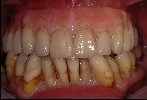

Vollkeramische Restauration auf eigenen Zähnen

- Vollkommen gesunde Situation des Zahnfleisches nach der Restauration mit vollkeramischen Kronen, keine schwarzen Ränder wie im Ausgangsbild (links) zu sehen.